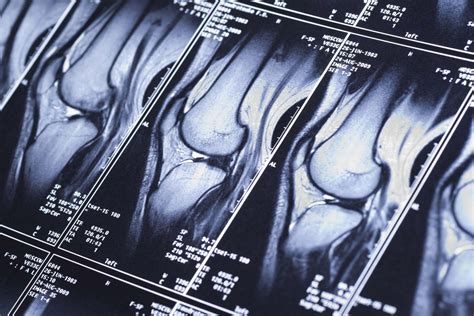

If you have recently experienced persistent joint pain, instability, or a specific injury, your healthcare provider may have recommended a diagnostic scan to get a clearer picture of what is happening inside your joint. Knee MRI images are the gold standard in diagnostic imaging for soft tissue injuries, providing incredibly detailed views that X-rays simply cannot match. Unlike X-rays, which primarily show bone structure, magnetic resonance imaging (MRI) uses powerful magnets and radio waves to create cross-sectional images of the ligaments, tendons, cartilage, and muscles that stabilize your knee. Understanding what these images show and why they are necessary can help demystify the diagnostic process and prepare you for your appointment.

Interpreting knee MRI images is a skill reserved for radiologists, who analyze the scan and produce a detailed report for your referring physician. However, having a basic understanding of what they are looking for can help you better understand your diagnosis. Radiologists look for changes in signal intensity; healthy tissue typically appears in a predictable pattern, while injured or diseased tissue will show up as "brighter" or "darker" areas, known as signal abnormalities.

The following table outlines how different knee structures typically appear on an MRI:

Structure Appearance on MRI

Bone (Cortical) Appears as a dark outer edge due to low water content.

Ligaments & Tendons Normally appear very dark (low signal) in all imaging sequences.

Meniscus Typically dark; bright signal within the meniscus often indicates a tear.

Joint Fluid Appears dark on T1-weighted images and bright on T2-weighted images.

Bone Marrow Variable signal intensity depending on fat and water content.